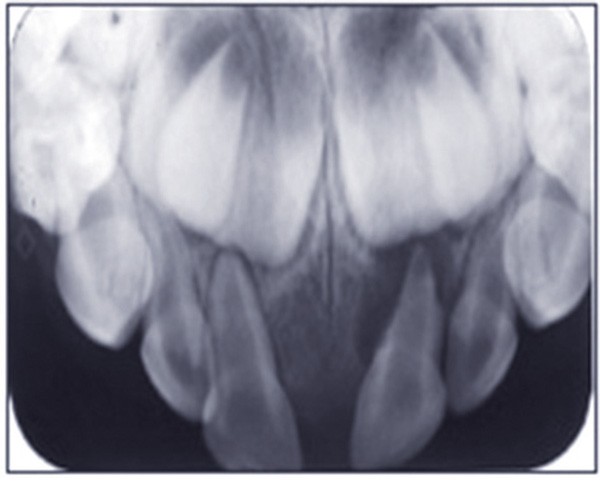

Les traumatismes des dents temporaires connaissent deux pics de fréquence entre 12 et 18 mois, et entre 3 et 4 ans. Ils interviennent donc souvent au cours de la croissance de l’appareil manducateur, avec de possibles conséquences sur le développement de celui-ci, et notamment sur les germes des dents définitives. C’est pourquoi le suivi des dents temporaires traumatisées jusqu’à la fin de la croissance est indispensable. Parmi les étapes qui doivent être surveillées, figure en premier lieu la formation de la dent définitive, qui sera surveillée radiographiquement. Son éruption peut également être perturbée par une dent temporaire traumatisée : le statut pulpaire de celle-ci sera surveillé cliniquement et radiographiquement. En effet, le risque infectieux subsiste après le traumatisme, et le suivi permettra d’éviter des cas de cellulites sévères. Si elle est nécessaire, l’extraction de la dent traumatisée pourra ainsi être réalisée au moment opportun. Enfin, dès la consultation qui a lieu après le traumatisme, les parents doivent être informés de l’importance du suivi, afin qu’ils y participent activement (fig. 1 et 2).

L’omnipraticien est très souvent confronté à cette question lors de sa pratique quotidienne : quel est le bon moment pour adresser les enfants chez l’orthodontiste ? La réponse peut recéler quelques difficultés, car elle est spécifique à chaque enfant. Le temps où il était conseillé d’attendre la denture définitive pour intervenir est révolu : certaines interventions précoces permettent aujourd’hui dans certains cas de raccourcir et de simplifier les traitements orthodontiques. C’est notamment le cas des anomalies transversales, qui sont celles qui sont traitées le plus précocement, dès 6 ans. Ainsi, lors d’anomalie cliniquement évidente, la consultation orthodontique s’impose. Cependant, certaines anomalies sont plus discrètes, et donc plus difficiles à dépister. Une panoramique doit toujours être réalisée en première intention afin de dépister les agénésies. Puis, même en l’absence d’anomalie évidente, il est recommandé d’adresser les enfants chez l’orthodontiste entre 7 et 9 ans : celui-ci sera ainsi à même d’adapter la prise en charge, et surtout l’âge idéal de prise en charge pour chaque patient(fig. 3 et 4).